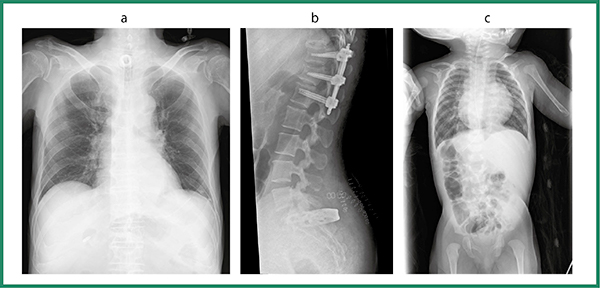

本製品は,富士フイルム社製としては,初めて取り組んだ移動型デジタルX線撮影装置であり,企画,開発から販売開始に至るまで困難の連続であったが,2016年11月の発売以来,導入が徐々に進んでおり,実際に臨床使用したユーザーからの反応が集まり始めている。特に,軽量な取り回しや使い勝手は好評であり,これまで使用されていた大型回診車と比べても遜色のない画像が得られている(図5)とのお言葉もいただいている。また,白色を基調とした医療機器が多い中,高機能性の印象や所有感を高めることをねらった黒/銀のカラーリングに対しては懸念もあったが,ユーザーからは「格好良い」や「斬新」と評価されている。このようなユーザーからいただく満足の声は,われわれメーカーにとって何よりの喜びである。

図5 CALNEO AQROで撮影した臨床画像の例

a:胸部画像(90kV,1mAs,120cm)

b:腰椎画像(100kV,5mAs,120cm)

c:新生児胸腹部画像(70kV,0.32mAs,120cm)